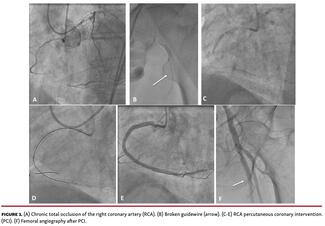

Guidewire-related complications are rarely reported, but are significantly associated with mortality and morbidity. Although radial approach is preferred in the majority of cases, femoral approach is needed in some complex procedures;...